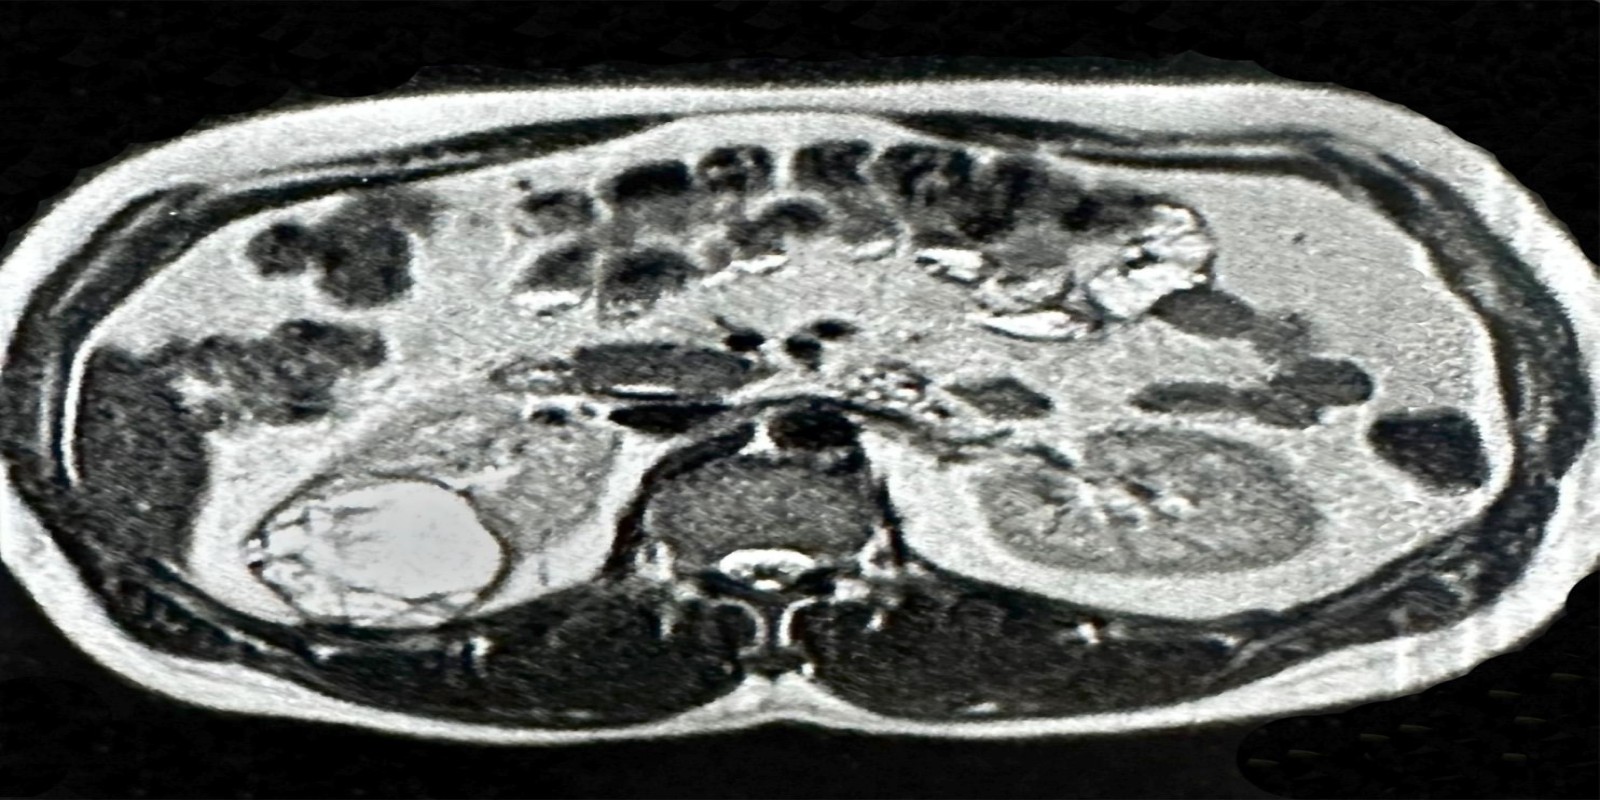

Tumor de células claras

Clear Cell Renal Carcinoma